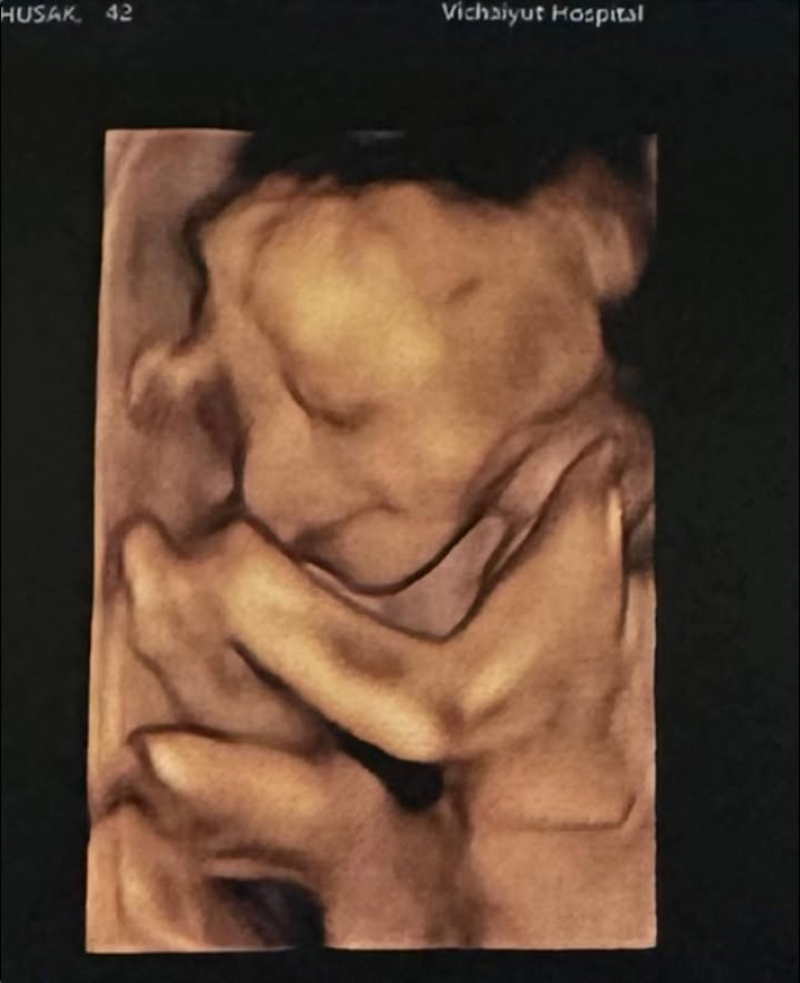

ล่าสุด เจมส์ ได้ออกมาโพสต์ภาพอัลตร้าซาวด์ของเบบี๋คนที่สองผ่านอินสตาแกรม พร้อมแคปชั่นน่ารักว่าแม่หนูมีเมตตาของฉันจมูกโด่งยิ้มหวาน